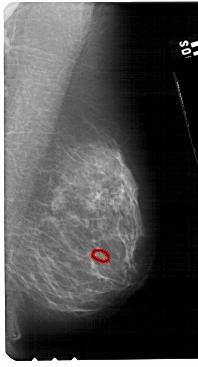

A_1310_1.RIGHT_MLO

RIGHT_MLO LINES 5491 PIXELS_PER_LINE 2956 BITS_PER_PIXEL 12 RESOLUTION 43.5 OVERLAY

FILE: A_1310_1.RIGHT_MLO.OVERLAY

TOTAL_ABNORMALITIES 1

ABNORMALITY 1

LESION_TYPE CALCIFICATION TYPE PLEOMORPHIC DISTRIBUTION CLUSTERED

ASSESSMENT 4

SUBTLETY 1

PATHOLOGY BENIGN

TOTAL_OUTLINES 1

BOUNDARY